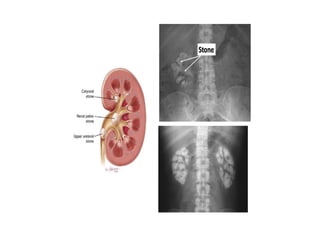

Thì không thuốc

• Khảo sát:

- Sỏi,	vôi hóa

- Xuất huyết,	tụ máu

- Mỡ đại thể trong u	thận

dạng đặc

- Tính mức độ bắt thuốc

trong các loại u

Sỏi thận+	vôi hóa động mạch

chủ bụng